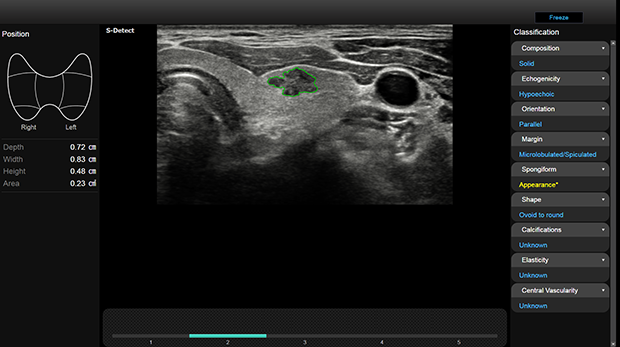

Le innovative tecnologie proprietarie di Samsung supportano la diagnosi assicurando un maggiore dettaglio e velocizzano i flussi di lavoro.